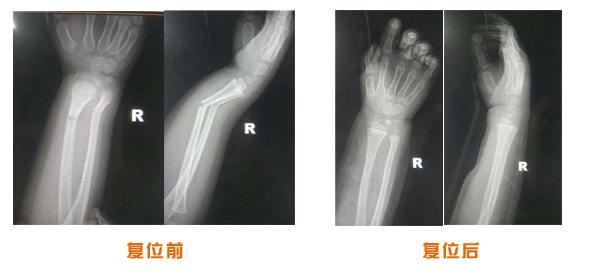

肥城市安駕莊梁氏骨科醫(yī)院是一所以梁氏手法正骨配合膏藥為特色的現(xiàn)代化??漆t(yī)院。

梁氏骨科術(shù)始創(chuàng)于清雍正年間,歷經(jīng)八代,至今已有三百年歷史。據(jù)1929年泰安縣志載“梁瑞圖先生,字增生,號蓮峰,安駕莊人,精岐黃并發(fā)明接骨,凡跌打車凡跌打車軋皮不破而碎骨者......【詳細】 |